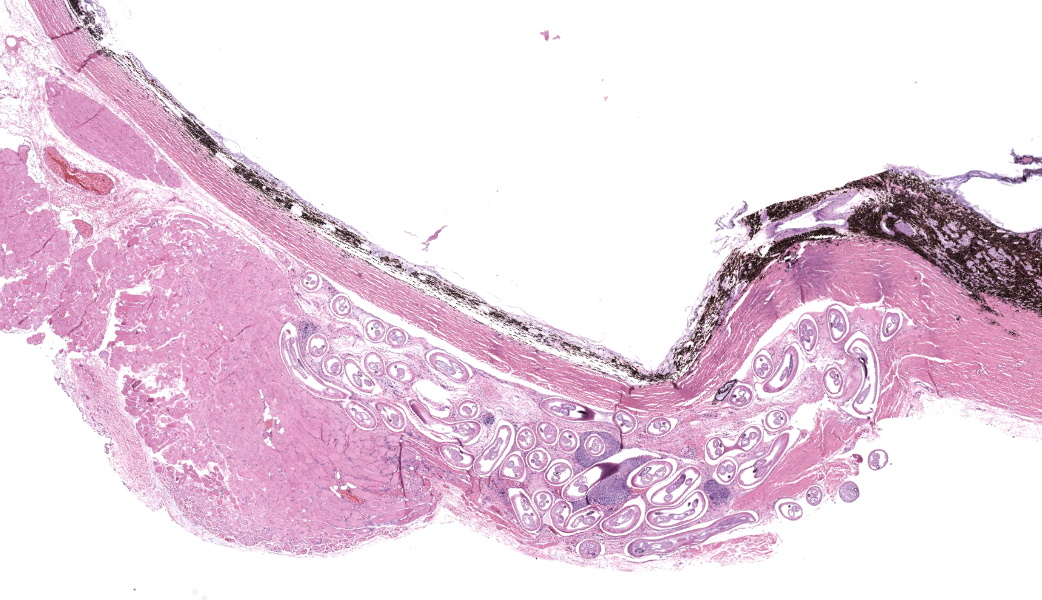

Enucleated right eye: Expanding and infiltrating the sclera, and occasionally extending to and dissecting the periocular skeletal muscle, are multiple cross and oblique sections of nematode parasites. Nematodes are characterized by a thick cuticle with annular ridges seen as raised areas in oblique sections, coelomyarian/polymyarian musculature that is atrophied and multifocally replaced by hypodermal tissue, a very small intestinal cross section, and reproductive organs. Mild hemorrhage, fibrin, and edema are present in affected sclera, and occasional nematode cross sections are surrounded by epithelioid macrophages. The cornea is hypercellular with low numbers of neutrophils and areas of neovascularization.Contributor's Morphologic Diagnoses:

Clinically, canine cases of Onchocerca lupi may present with single or multiple, variably sized nodules on the bulbar conjunctiva, conjunctival hyperemia, episcleral injection, chemosis, periocular swelling, retinal detachment, and corneal edema.13,14 Typical gross lesions include nodules affecting the conjunctiva, episcleral tissue, and periorbital soft tissues.13 Some cases do not have reported clinical signs directly attributable to Onchocerciasis, and are diagnosed as an incidental lesion on biopsy secondary to other presenting causes like neoplasia.13 Bilateral involvement is described.14

Onchocerca lupi is typically diagnosed via histopathology, and to our knowledge no commercially available polymerase chain reaction (PCR) tests is available, although PCR assays have been described in the peer reviewed literature.7,14 Typical histologic lesions include nematodes with very small intestinal cross sections, atrophied coelomyarian/polymyarian musculature, and annular cuticular ridges that can be seen in longitudinal or oblique sections. Microfilaria may be seen within female worms. Variable amounts of inflammation ranging from mild to severe, and including macrophages, lymphocytes, and eosinophils may be seen, as can fibroplasia. We have seen pyogranulomatous inflammation as well in our laboratory. Currently, a commercially available serology test is not available, although serologic tests are in development.15

- Globe and periocular tissue: Scleritis and orbital rhabdomyositis, granulomatous, chronic, multifocal, moderate, with adult filarids.